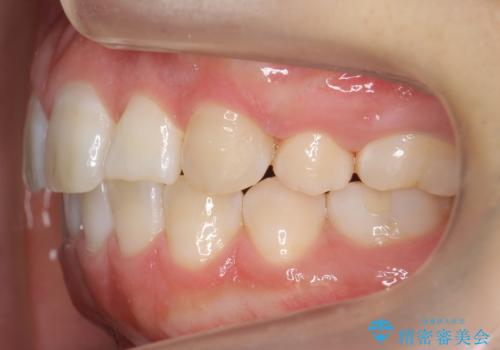

- 2年3ヶ月

最小限の抜歯により矯正ができたと、喜んでいただきました。